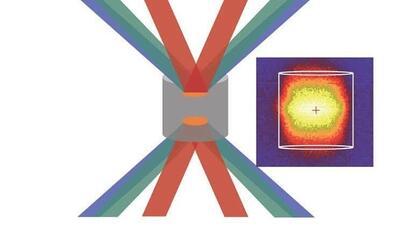

اشعه ایکس با دوز پایین میتواند سلولهای تومور مغزی را نابود کند!

پروفسور Pu Kanyi نویسنده ارشد و همکار این مطالعه گفت: «ما از دوزهای بسیار پایین اشعه ایکس و MRAPهای کشنده سرطان استفاده کردیم.